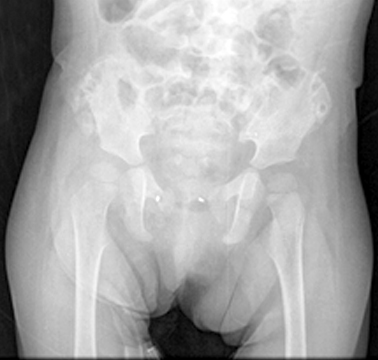

Se aplicaron antibióticos y se programó para la fijación interna definitiva del material de osteosíntesis. Este se hizo mediante un abordaje tipo Pfannenstiel, que consistió en liberar la zona prevesical y diseccionar los cartílagos del pubis; después se efectuó la maniobra de reducción, por fijación con pinzas e inserción de dos anclajes de 2.0 en titanio, clausura de la sínfisis y paso de doble sutura (fig. 4) para cerrar el anillo pélvico. Por último, se colocó inserción musculotendinosa, se lavó exhaustivamente, mientras se remataron la fascia y la piel con Prolene, el vendaje y la sonda vesical se dejaron por 8 horas.

Las radiografías de control de pelvis mostraron adecuada reducción (fig. 5). La paciente egresó a las 48 horas con órdenes de analgesia, antibiótico por cinco días, terapia física diaria durante 10 días y cita de control a las dos semanas. En la consulta ambulatoria, se observó una evolución clínica satisfactoria, la herida quirúrgica en adecuado estado, sin signos locales de infección, ni alteración vascular, motora o sensitiva, en las extremidades; aunque los rangos de movilidad se mantenían conservados (fig. 6).